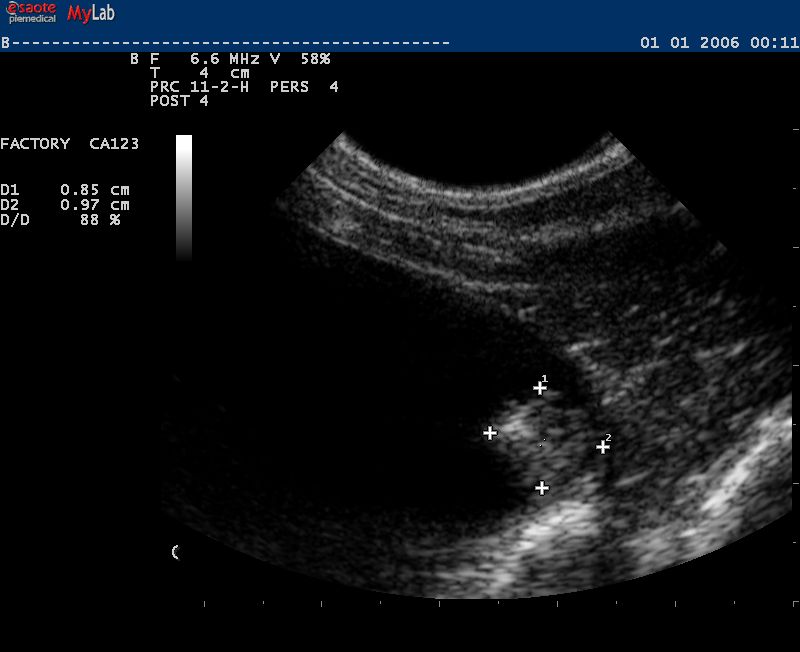

Auch in der Veterinärmedizin wird das schonende Verfahren der Ultraschalldiagnostik zunehmend eingesetzt. Wir verwenden es im Bereich der Abdominal- und Trächtigkeitsdiagnostik .